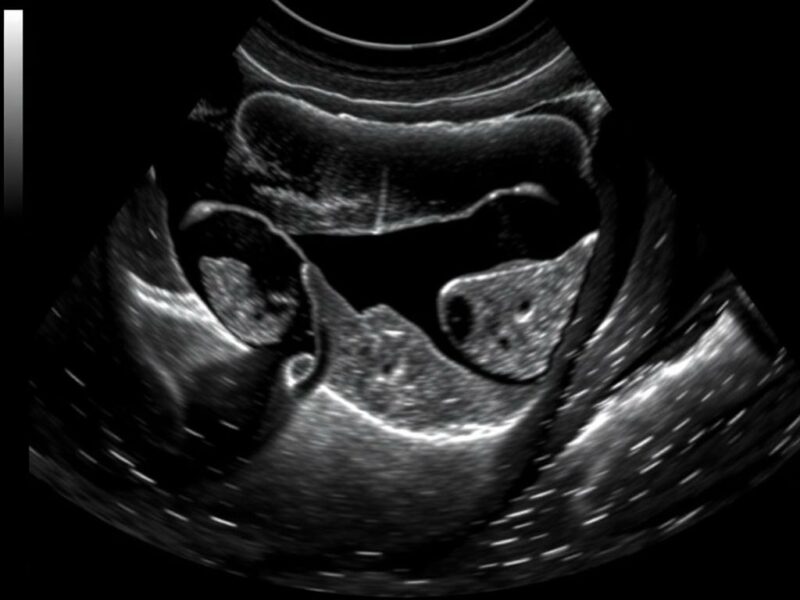

Riñones y vía urinaria

La evaluación renal busca hidronefrosis (dilatación del sistema colector), litiasis, masas o quistes complejos. En dolor lumbar o sospecha de obstrucción urinaria, identificar dilatación pielocalicial orienta a obstrucción alta; en sepsis de origen urinario, comprobar reinante o colección perirrenal. El aporte Doppler ayuda cuando se sospecha trombosis venosa renal o isquemia.

| Hidronefrosis con dilatación pielocalicial | Obstrucción ureteral / litiasis | Analgesia, control de infección y urología |